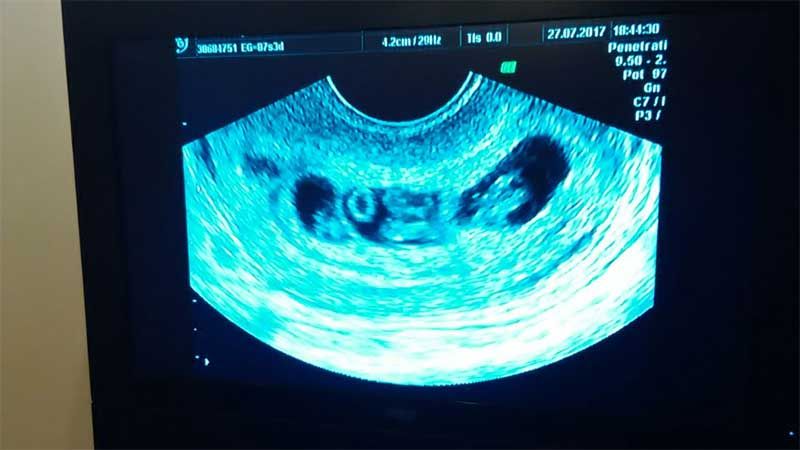

La primera ecografía / Los gemelos al medio y los mellizos en cada costado

Es un caso único en el mundo, ya que, si bien los embarazos múltiples se dan a menudo, nunca antes se vio el tipo de Yanina y de Matías, que serán padres de gemelos y mellizos a la vez, ¡por primera vez!

Yanina cursa un embarazo de alto riesgo, por lo que su ginecóloga le diagnosticó reposo absoluto, entre otros cuidados que está tomando desde el primer día. Hoy cursa el tercer mes de gestación - “y tengo panza como si estuviese de cinco” - y estiman que los bebés nacerán entre el sexto y el séptimo mes.